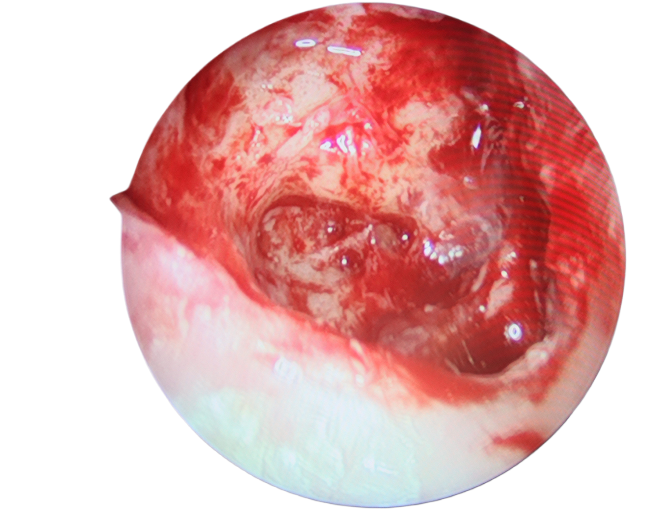

手術(shù)中,使用微動(dòng)力系統(tǒng)及耳電鉆磨開乳突骨質(zhì),在乳突氣房中發(fā)現(xiàn)大量膿性分泌物,取以刮匙清理干凈。隨后,又在顱內(nèi)硬腦膜外發(fā)現(xiàn)大量膽脂瘤型分泌物,遂予徹底清除。